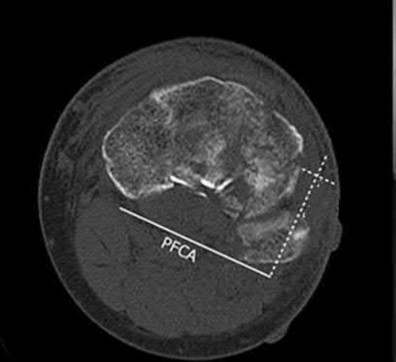

The patient presents with a closed distal third metaphyseal-diaphyseal distal tibia fracture with simple intra-articular extension. Immediate intramedullary nailing along with percutaneous fixation of the articular component provides appropriate restoration of length, rotation and alignment and minimizes the risk of wound complication.

Displaced distal third tibia fractures may be associated with simple intraarticular extension. Operative treatment of intra-articular distal tibia fractures has historically been performed with open reduction and internal fixation. Early open reduction and plate fixation of pilon fractures has been associated with high rates of infection and wound complication. In select patterns with simple articular extension, percutaneous screw fixation and medullary nailing may provide appropriate reduction with minimal soft-tissue risk.

Figures A and B demonstrate a distal third tibial shaft fracture with simple intra-articular extension. The axial and coronal CT cuts in Figures C and D further clarify the articular injury. Illustrations A and B demonstrate a comminuted distal third tibial fracture with simple intra-articular extension. Illustrations C and D are fluoroscopic images of the same injury after intramedullary nailing and percutaneous fixation of the articular component.

A 25-year-old female is involved in a motor vehicle collision. She presents with the isolated injury seen in Figures A through D. Her leg is swollen but her skin is intact. She has no clinical signs of compartment syndrome. Which of the following treatment options will allow for maintenance of fracture alignment and minimize the risk of soft tissue complications?